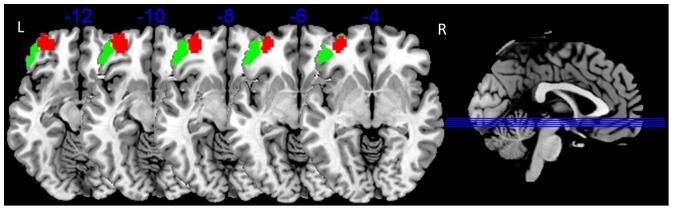

Compared to HC, MDD patients showed reduced ALFF in the bilateral OFC and increased ALFF in the bilateral temporal lobe extending to the insular and left fusiform cortices. Enhanced anti-correlation of activity between the left amygdala seed and the left OFC was found in MDD patients but not in HCs.

与 HC 相比,MDD 患者双侧 OFC 的 ALFF 降低,双侧颞叶(延伸至岛叶和左侧梭状回)的 ALFF 增加。MDD 患者左杏仁核种子与左 OFC 之间的活动反相关增强,但 HCs 中未发现这种相关性。